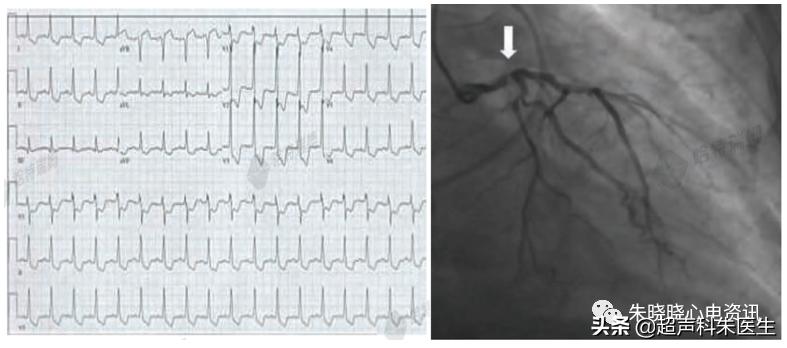

病例1:左主干病变或等危症

如图16所示,89岁男性,因胸痛1周,加重1小时入院。心肌损伤标志物增高,急诊室考虑急性冠状动脉症状 (ACS) ,遂予急诊冠状动脉血管造影 (CAG) ;冠脉造影示:左主干近端严重狭窄 (箭头所指) ,右冠完全闭塞,由左冠脉发出的侧枝循环供应 (未见图像) 。

图16:广泛导联T波倒置及左主干近端严重狭窄

心肌缺血引起的T波倒置主要与动作电位时限延长有关。在心梗 (MI) 急性期,广泛导联的T波倒置往往能提示出现了大范围的心肌顿抑,部分病人可伴有QT间期延长或aVR导联ST段抬高。